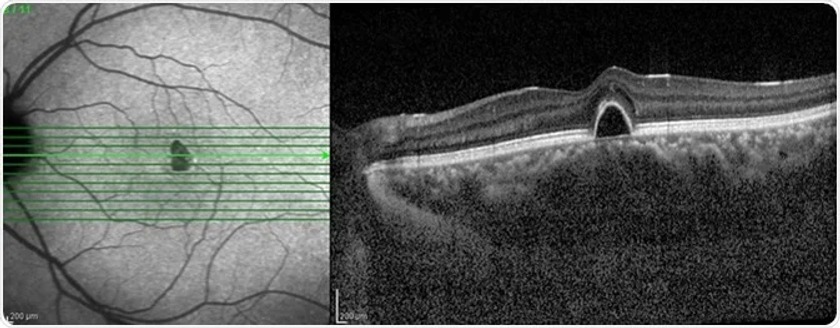

1. Optical Coherence Tomography (OCT) & OCT-Angiography

This non-invasive imaging technique uses light waves to create cross-sectional images of the retina, optic nerve head, and other structures at a microscopic level, aiding in the assessment of conditions like optic neuritis, optic nerve atrophy, and other neuro-ophthalmic disorders. Additionally, OCT angiography helps in diagnosing and monitoring ischemic optic neuropathy that occurs in diabetic and hypertensive patients.

Causes: Small Vessel Disease: Poor blood flow to the optic nerve due to conditions like diabetes, high blood pressure, or sleep apnea. Optic Disc Structure: A crowded optic disc can increase the risk, often found in people with a "disc at risk."

Diagnosis: Clinical Examination: Assessment of vision, optic disc appearance, and medical history. Imaging Tests: Optical coherence tomography (OCT) can help visualize the optic nerve and surrounding structures. Blood Tests: To check for underlying conditions like diabetes or high cholesterol.